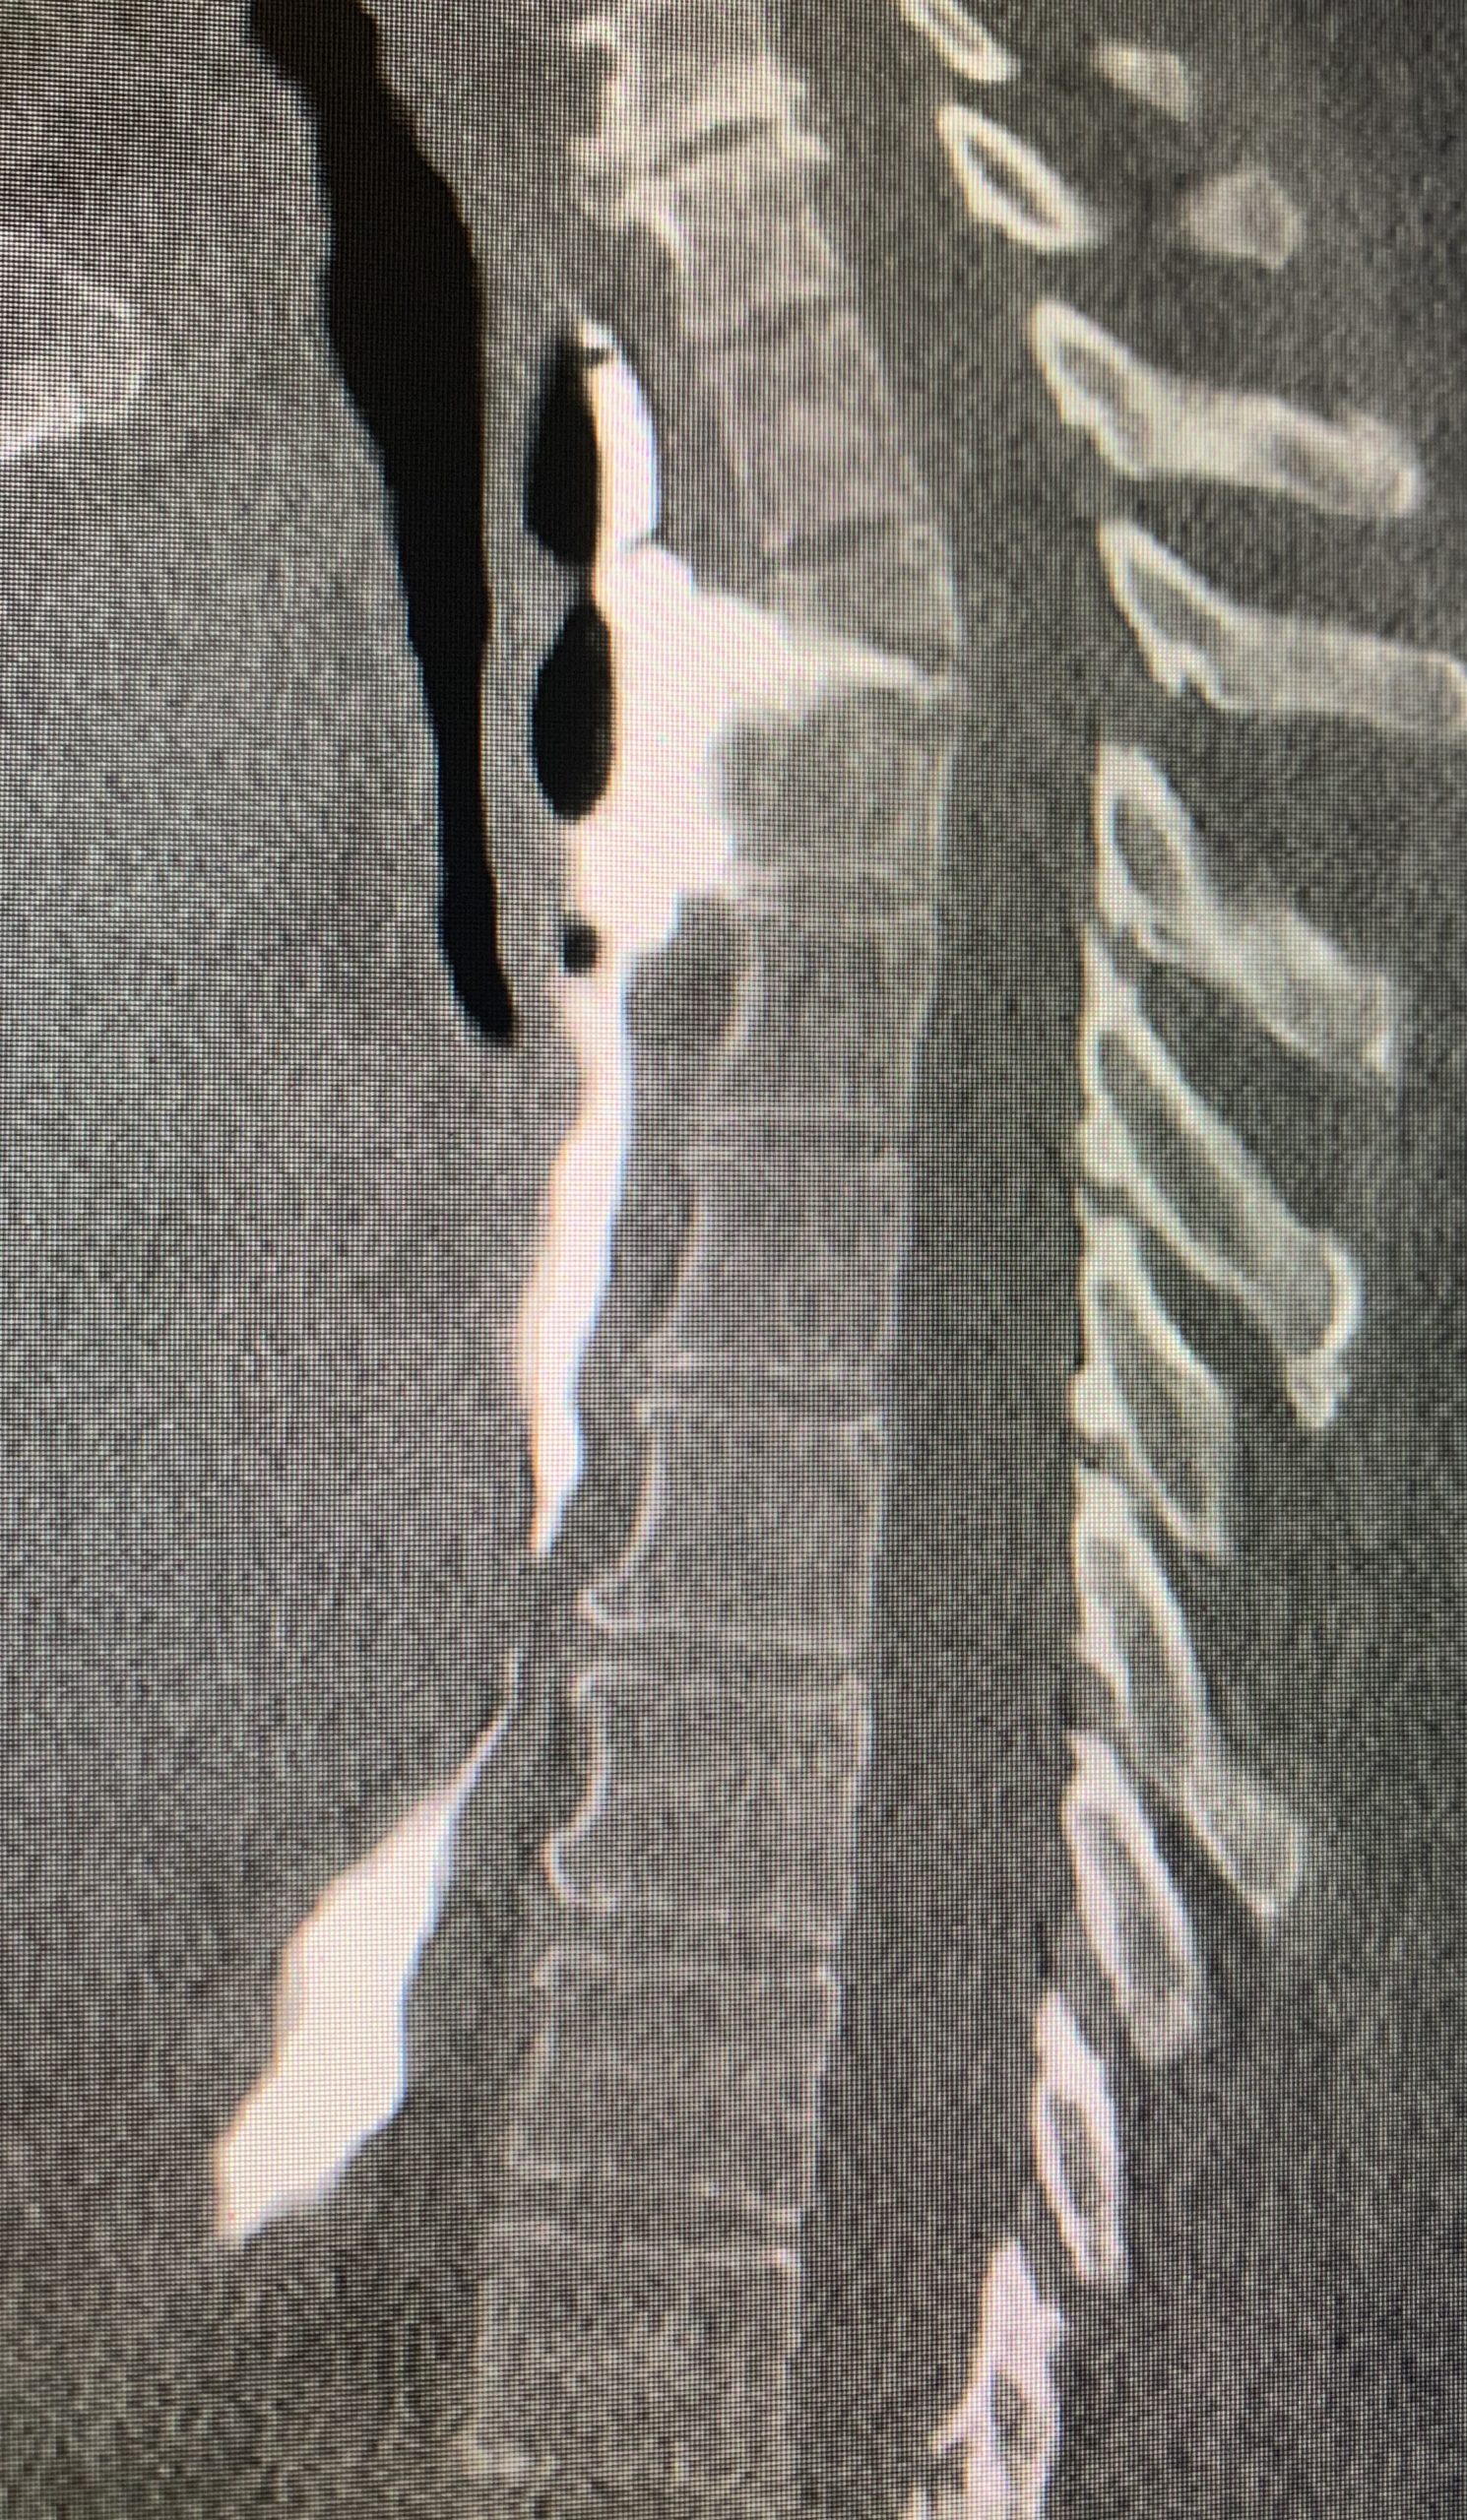

Case Presentation: Epidural-Esophageal fistula is an uncommon adverse event after esophageal perforation. The presenting symptoms may mimic other more common conditions, which may lead to incorrect diagnosis. We present a patient with esophageal perforation of unknown etiology, complicated by spinal epidural abscess.52-year-old female with a history of liver cirrhosis secondary to hepatitis C, endometrial carcinoma with metastasis to lung for which she received radiation therapy, hypertension and diabetes mellitus presented to the hospital with cough, fever and shortness of breath. Computer tomography scan (CT) showed a loculated effusion and a thoracostomy tube was placed. Microbiology cultures from the chest tube showed infection with GDS, Klebsiella, Eubacterium, VSE. She received vancomycin and unasyn, and the thoracostomy was removed. Subsequently, the patient developed acute back pain that prompted to get a magnetic resonance imaging (MRI) showing destruction of the endplates at T2-T3, a paravertebral and epidural abscess as well as an esophageal leak at the same level. Barium esophagogram revealed a 3.5 cm contained leak of the mid-upper esophagus. Antibiotic therapy with cefepime was started. Since the esophageal leak was contained and patient did not have any neurologic complaints at the time, the decision was made for no surgical intervention. An esophageal/endoluminal wound vac (WV) and PEG tube was placed as well, in an attempt to seal the leak and bypass the defect.